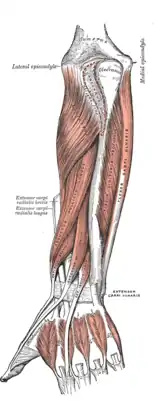

Superficial muscles of the forearm

Superficial muscles of the forearm Deep muscles of the anterior forearm

Deep muscles of the anterior forearm Deep muscles of the posterior forearm